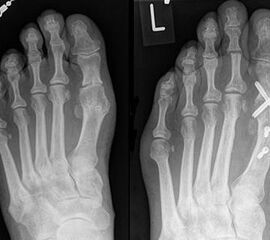

Die dorsoplantaren Röntgenaufnahmen zeigen eine Open-wedge Technik mit der normalerweise ein erhöhter intermetatarsaler Winkel gut zu korrigieren ist (Abbildung 3). Die Wirksamkeit einer Basisosteotomie ist umso größer, je proximaler diese durchgeführt wird. Je weiter distal die Osteotomie, umso geringer die Korrektur. Auf den postoperativen Bildern ist der distal unverändert große Abstand zwischen Metatarsale I und Metatarsale II erkennbar, bei gleichzeitiger Subluxation des Großzehengrundgelenks und dezentrierten Sesambeinen. Darüber hinaus finden sich initiale degenerative Veränderungen im Großzehengrundgelenk. Klinisch bestand eine hohe Weichteilspannung, bei verkürzter Extensor- und Flexor hallucis longus Sehne.  Daher wurde ein verkürzendes Verfahren zur Revision gewählt (Abbildung 4). Die Lapidusarthrodese stellt ein sehr zuverlässiges Verfahren zur Behandlung von Hallux valgus Rezidiven dar 9. Die Fusion des Tarsometatarsale-I-Gelenks kombiniert Stabilität mit einem hohen Korrekturpotenzial. Aufgrund der verfahrensimmanenten Verkürzung des ersten Strahls und der in diesem Fall bereits präoperativ vorhandenen Transfermetatarsalgie wurde die Entscheidung für eine verkürzte Weil-Osteotomie am zweiten bis fünften Strahl gefällt. Die Kombination beider Verfahren führte zu einem homogenen Metatarsale-Index und zu einer gleichmäßigen plantaren Druckverteilung 10. Die Hallux valgus interphalangeus Fehlstellung wurde mit einer Akin-Osteotomie korrigiert.